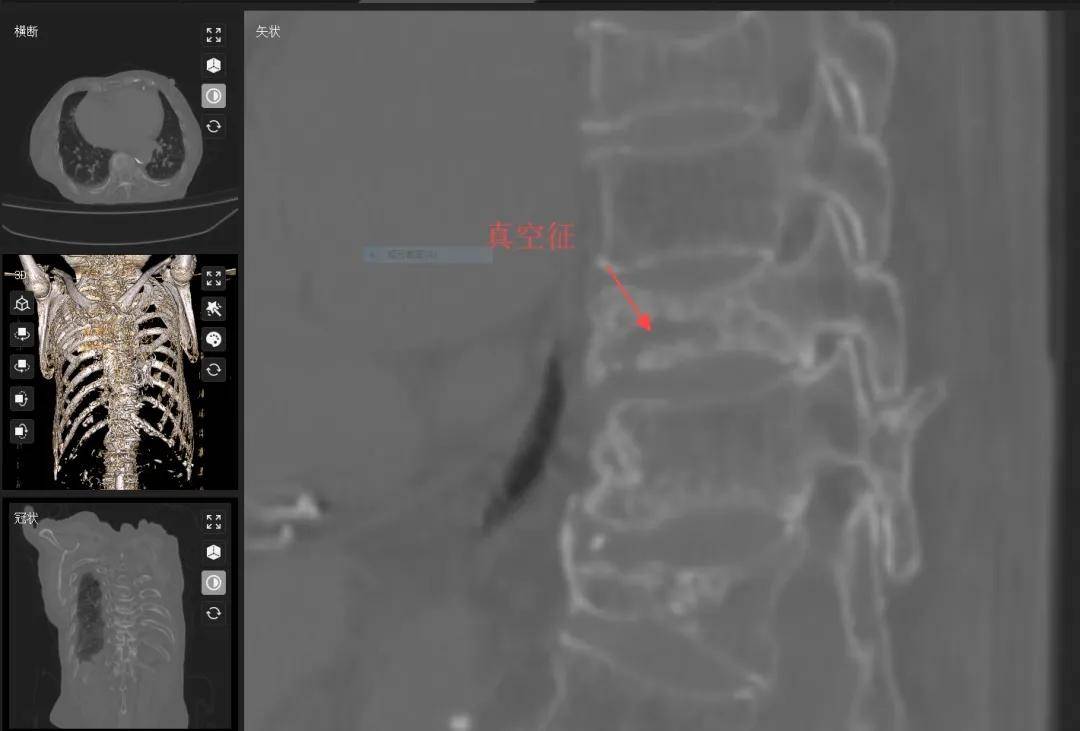

“腰像被石头压着,站都站不起来!”88岁的李奶奶因严重驼背、无法站立被家人紧急送医。经叶军博士后团队检查发现:她的胸腰椎竟连续3节骨折,骨内出现“空泡”(Kümmell病)!深入分析发现,常年忽视的背部肌肉严重萎缩是祸首——肌肉流失后,骨质疏松的脊柱如“失索悬桥”,不堪重负导致塌陷性骨折。